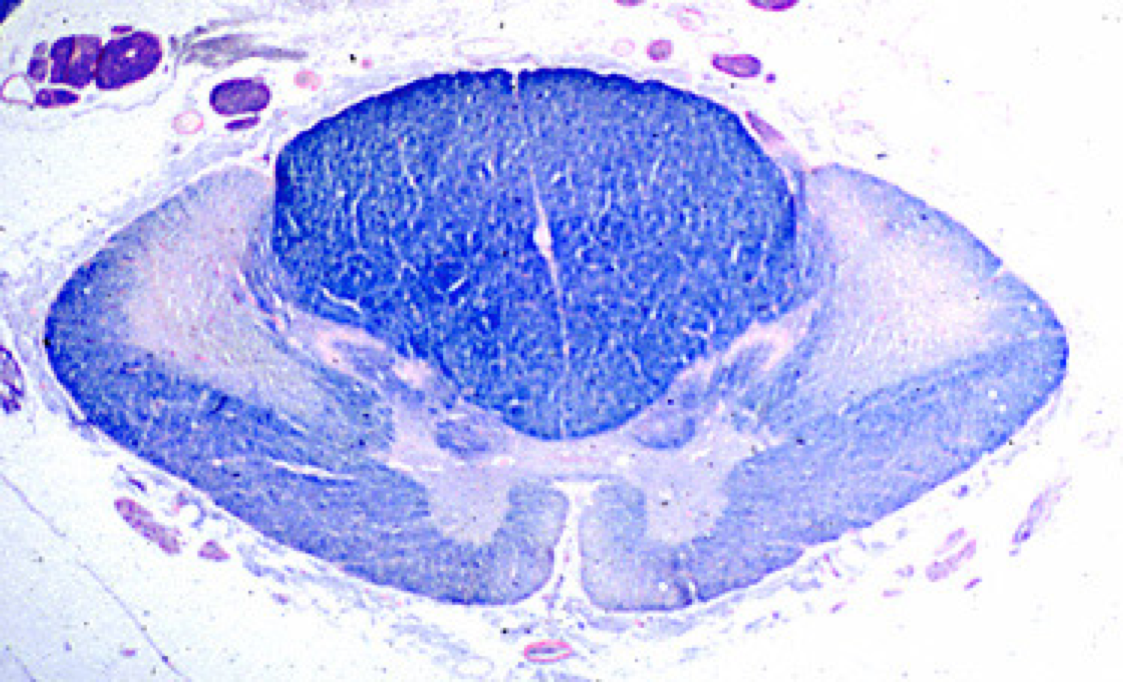

ALS - degeneration of corticospinal tracts with sparing of other tracts